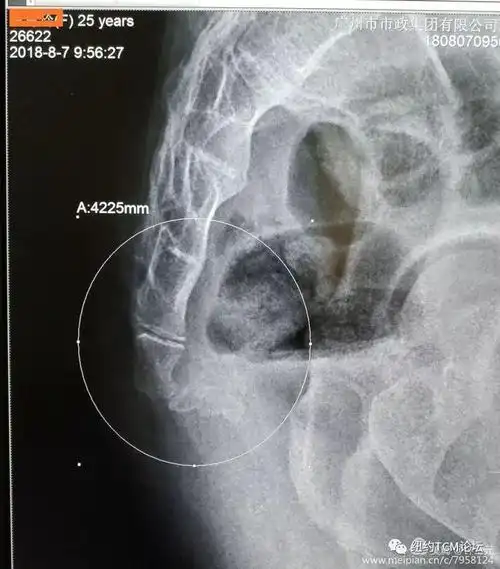

钟士元▏少见的尾椎变异▏纽约中医论坛